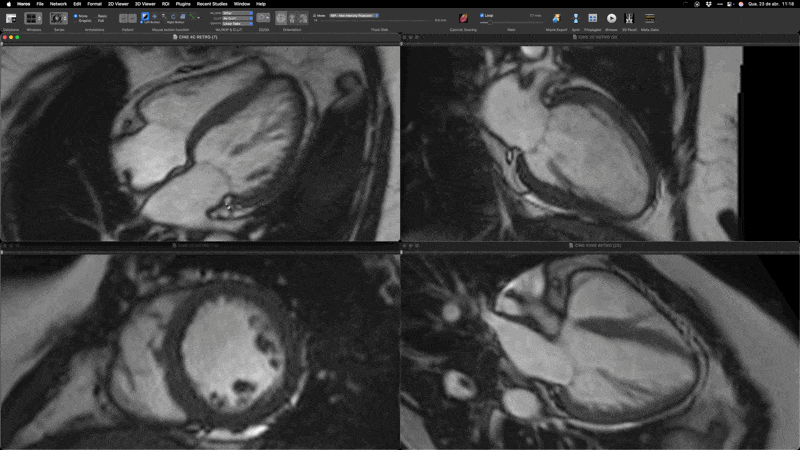

É um exame de imagem não invasivo que utiliza um forte campo magnético e ondas de rádio (sem radiação ionizante) para criar imagens de alta definição do coração e grandes vasos.

Geralmente envolve o uso de contraste à base de gadolínio (exceto em casos específicos) para avaliar detalhadamente a estrutura, função, músculo cardíaco (miocárdio), válvulas, fluxo sanguíneo e caracterizar tecidos (inflamação, fibrose).

Indicada para investigar causas de insuficiência cardíaca, cardiomiopatias, miocardite, avaliar danos pós-infarto, doenças congênitas, massas cardíacas, entre outras condições.